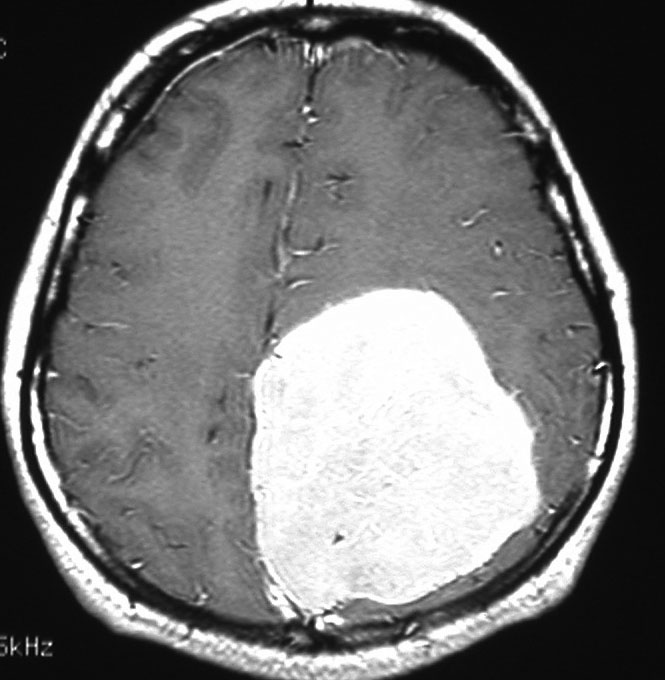

最も見やすいのが,ガドリニウム造影剤を注射して撮影するものです。一般的に髄膜腫は造影剤で白く映し出されます。この腫瘍は左脳側にあります。MRIの軸面という輪切りの写真では左右が逆になりますから注意してください。脳を下から見た図になっています。MRIはいろいろな方向から腫瘍を見ることができますが,右は冠状断という正面から見た図です。よく見ると腫瘍の上と下のはじっこに線状に糸を引いたように造影される部分があります。これをテールサイン(しっぽのサイン)といいます。腫瘍が硬膜に沿って延びている可能性があることを示しています。

手術後のMRIです。腫瘍は全部取れていて後遺症もありません。圧迫されて変形していた脳はきれいに元に戻っていますし脳浮腫も消えました。一般的に若い人の脳ほどきれいに元に戻ります。注意しなければならないのは,少しでも取り残した場合には,何年か後に10%-20%くらいで再発があることです。もちろん完全に取れた時の再発はほとんどありません。